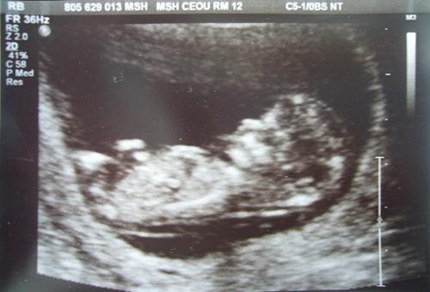

nub theory指的是通过NT检查图片上的胎儿特征点和尾椎的角度判断男女,男孩的特征点与身体呈45度角,还多一些,而女孩儿的特征点几乎和躯体平行。还有就是如果是男宝宝,屁股位置会微微上翘,后背脊柱成圆弧状,因为要留空间发育前列腺,相反,女宝宝后背脊柱就相对就平一些。

Between 11-13 weeks, all babies are said to have a 'nub' between their legs, and the angle of the nub will indicate whether it's a boy or girl.

十一至十三周,所有的胎儿都会在双腿之间长出一个小肿块,而这个肿块的角度则会显示出它是个男孩还是女孩。

It's said that if the nub is over 30 degrees up, it's a boy - but if it's under that then it's a girl. See our pictures below as an example.

据说如果小肿块翘起来30度以上就是男孩,但如果小角度就是女孩。请看下面的例子。